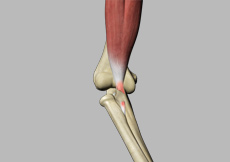

Bicep Tendon Tear at the Elbow

The biceps muscle, located in the front of the upper arm allows you to bend the elbow and rotate the arm. Biceps tendons attach the biceps muscle to the bones in the shoulder and in the elbow.